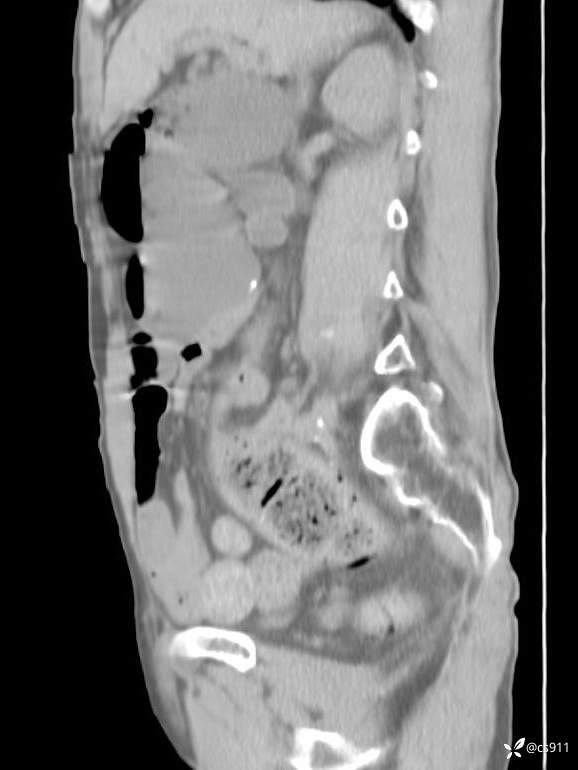

急腹症之急诊CT,原因?答案公布

男,77岁,腹痛、腹胀伴恶心呕吐1天。呕吐胃内容物,非喷射性呕吐,有咖啡色样胃内容物,诉有胃穿孔病史。查体:全腹平,下腹部压痛,全腹无反跳痛,叩诊呈浊音,移动性浊音阴性,肠鸣音减弱,1-2次/分。肛检:直肠未扪及明显肿物,可触及大量粪块。

T 36.6℃ P 80次/分 R 26次/分 BP 100/60mmHg

白细胞(WBC) H 14.55 10e9/L 4-10

中性粒细胞百分率(NEUT%) H 85.7 % 40-75

血淀粉酶(AMY) HH 1859 U/L 35-135

癌胚抗原(CEA) H 27.44 ng/ml 0-5

呕吐物 潜血试验 * 阳性 阴性

患者轮椅入室检查神志清楚, 能配合摆位和呼吸